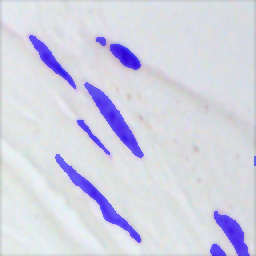

The qualitative results for the proposed and competing methods are shown in Fig. 3. The quantitative results comparison of the proposed method to the four state-of-the-art methods are shown in Table 1. The results reveal that the proposed method comfortably outperform other studied methods for smaller fractions of annotated data (e.g. Spleen 5%). The gap between the Duo-SegNet and other competitors decreases on the Nuclei dataset, when the amount of labeled data increases. That said, we can still observe a significant improvement on the Heart and Spleen dataset. The proposed network can produce both accurate prediction masks and confidence maps representing which regions of the prediction distribution are close to the ground truth label distribution. This is useful when training unlabeled data. Fig. 2 shows the visual analysis of confidence maps.

![]() |

| Input | GT | Prediction | Confidence Map |

|

Nuclei |